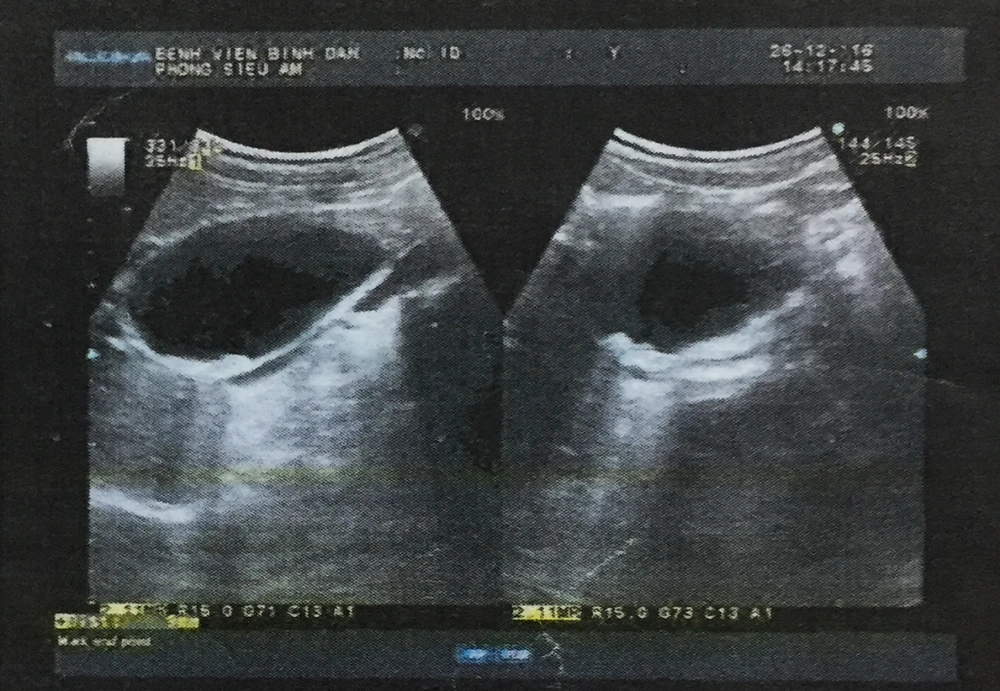

Kết quả CT Scanner cho thấy bệnh nhân có nang ống mật chủ kích thước gần 4X6cm. Tháng 12-2016, bệnh nhân T. đã được các bác sĩ chỉ định phẫu thuật nhưng do mới sinh con nên bệnh nhân được các bác sĩ chỉ định tiếp tục theo dõi ca bệnh.

Phẫu thuật ứng dụng robot để loại bỏ nang ống mật chủ, tránh những nguy cơ tái viêm nhiều lần.